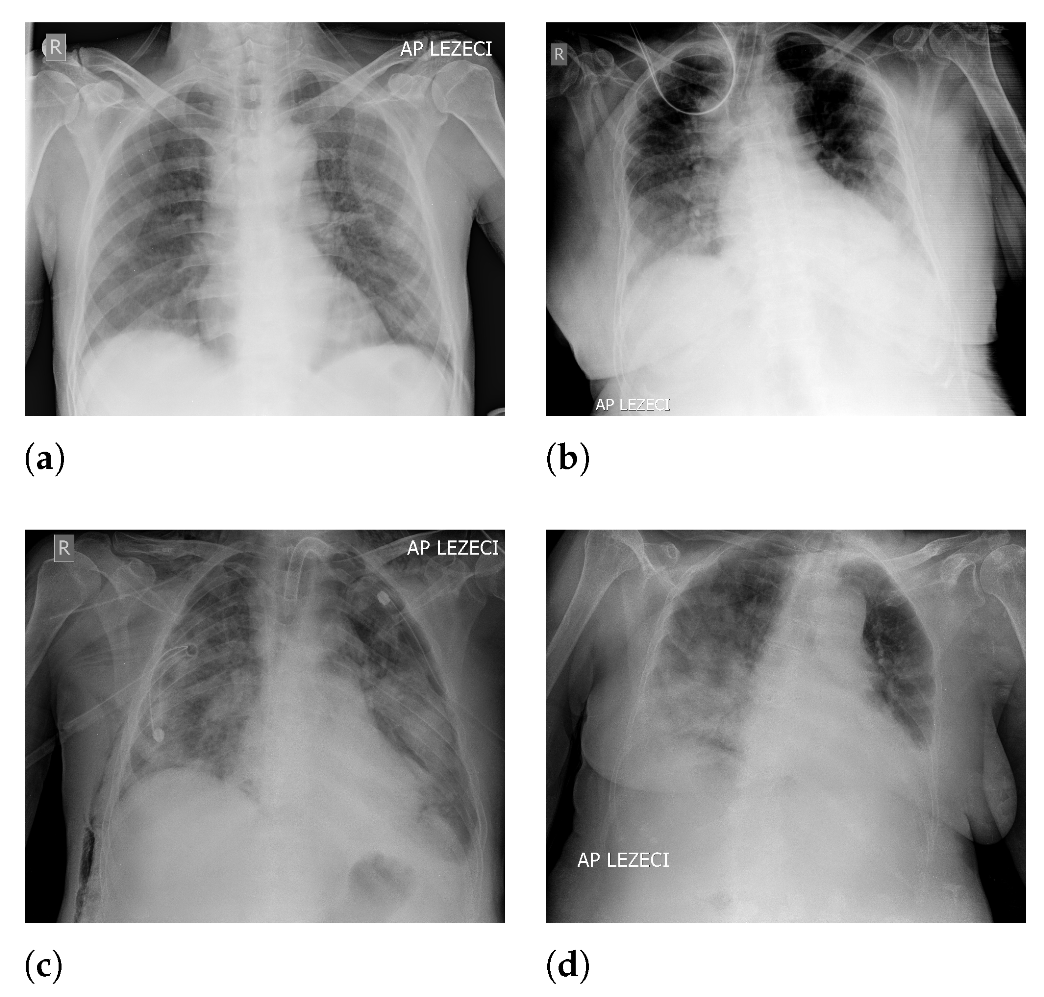

An overview of image classes has been presented in Figure 1, where each class is represented with a X-ray image.

Figure 1.

Examples of X-ray images contained in the dataset: (a) A mild clinical picture; (b) moderate clinical picture; (c) severe clinical picture; and (d) critical clinical picture.